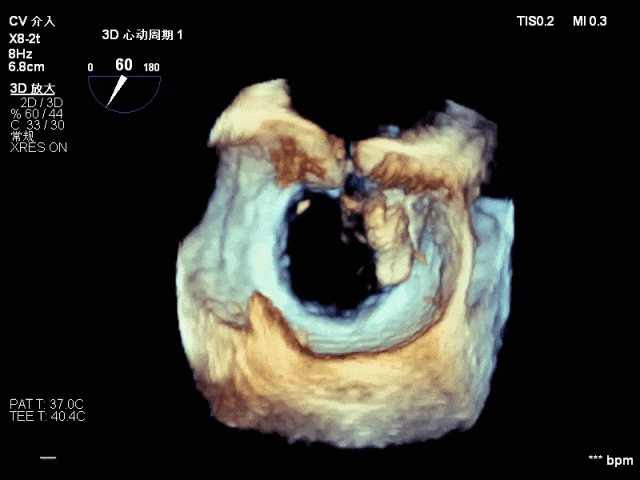

术前影像【交界联合彩色】

术中影像【于3区靠交界植入一枚短宽(SW0609)夹】